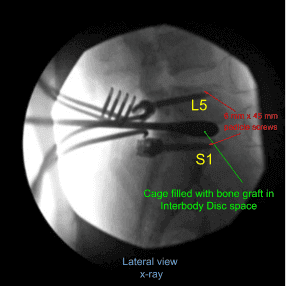

Una vez realizada la disección, se decidió colocar tornillos pediculares en ambos pedículos de S1 y L5. Se utilizaba un taladro para marcar un agujero piloto y una palanca de cambios para guiar el agujero a través del pedículo de S1 a ambos lados bajo guía fluoroscópica. Se utilizaba el sonido de la punta de la bola para comprobar la integridad del canal.

Luego se insertaron 40 mm x 6 mm de tornillos pediculares (Depuy Synthes) en cualquiera de los pedículos de S1 y se revisaron mediante fluoroscopia y se comprobaron que estaban en posición satisfactoria. De manera similar, se realizó un agujero piloto utilizando un taladro a ambos lados del pedículo de L5 seguido de una palanca de cambios para encontrar el camino bajo fluoroscopia. Se volvió a usar una sonda con punta de bola y se encontró que todas las paredes estaban intactas. De nuevo, se hacía el golpeteo y se insertaban tornillos pediculares de 6 mm x 45 mm en cualquiera de los pedículos.

Se insertó una jaula de prueba y se revisó con fluoroscopia y se decidió instalar una jaula de titanio de 9 mm x 36 mm. Se utilizó aloinjerto y se mezcló con injerto autoóseo morselizado de la lámina y proceso espinoso. El espacio entre la jaula y el disco se llenaron con injerto óseo y se insertó y revisó mediante fluoroscopia, encontrando una posición satisfactoria.